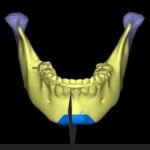

Aligner Planning

Into the world of invisible orthodontics with clear aligners. In house clear aliogners planning using orthoanalyser software.

3D Printing

Designiing, fabrication and printing of appliances with zero laboratory hassle. Printing of surgical splints, models, etc.